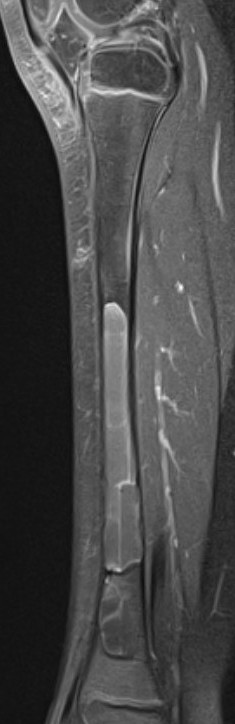

Surgical cyst drainage using implants

Concept

- venous hypertension cause of cyst

- if allow cyst to drain, will heal

Options

- cannulated screws in calcaneum

- flexible nails humerus

- intramedullary nail femur

Results

Erol et al J Paediatr Orthop B 2017

- humeral simple bone cysts

- 37 curettage and bone graft

- 16 had addition of flexible nails

- 76% healing curettage and bone graft

- 100% healing with flexible nails